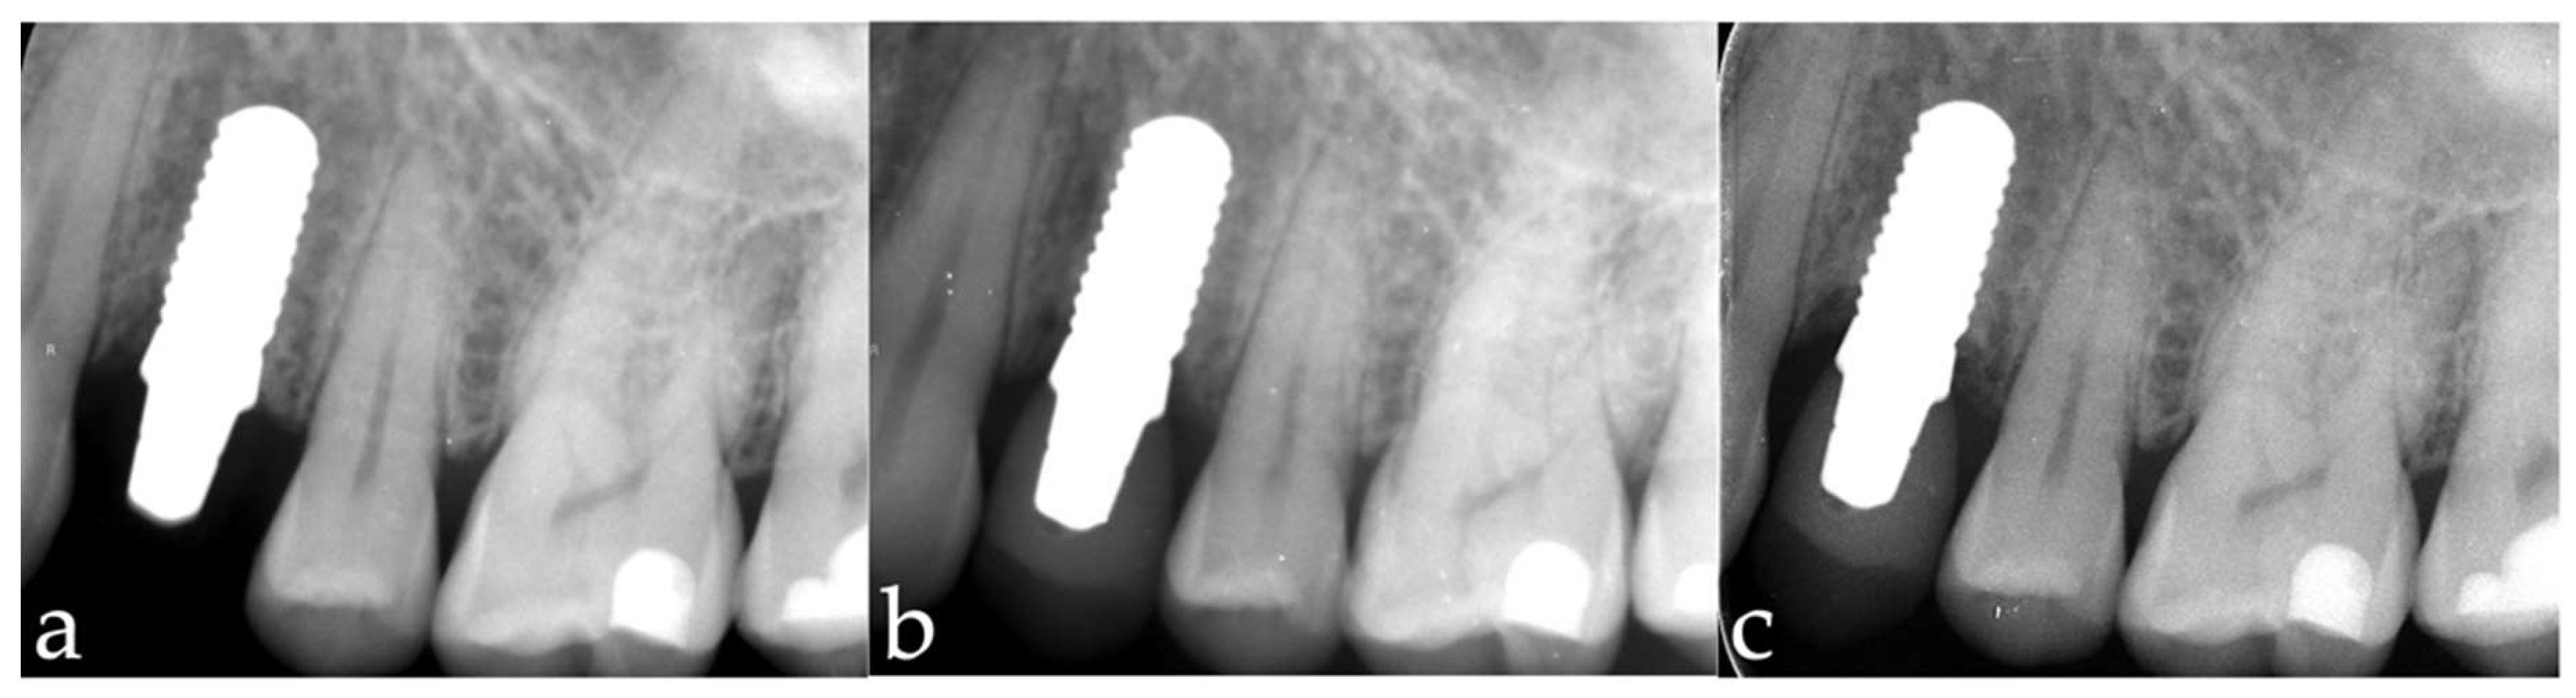

3.1. Marginal Bone-Level Changes